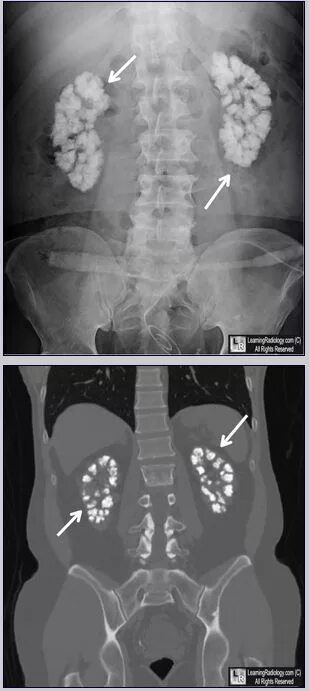

Рентген и мрт в чем разница